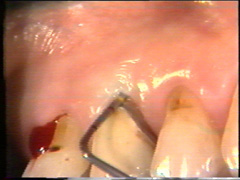

Varón de 50 años de edad que es enviado para tratamiento periodontal., nos comenta que ha sido tratado por el procedimiento de raspado y alisado radicular durante algún tiempo con un resultado limitado, observamos que tine una buena higiene dental pero las señales de patología periodontal continúan. La imagen muetra una lesión de furcación profunda en el primer molar superior con tejido gingival firme (Fibrosis) que limita el acceso al fondo de la bolsa por el método no quirúrgico y también la presencia de cálculo subgingival neutraliza la penetración de la sonda en la región dentogingival. |

La anatomía de la lesion de furcación puede ser difícil de registrar usando la sonda periodontal ordinaria. Una cureta delgada o una sonda doblada para dicho propósito es una gran ayuda para descubrir la morfología de la lesión de furca. |